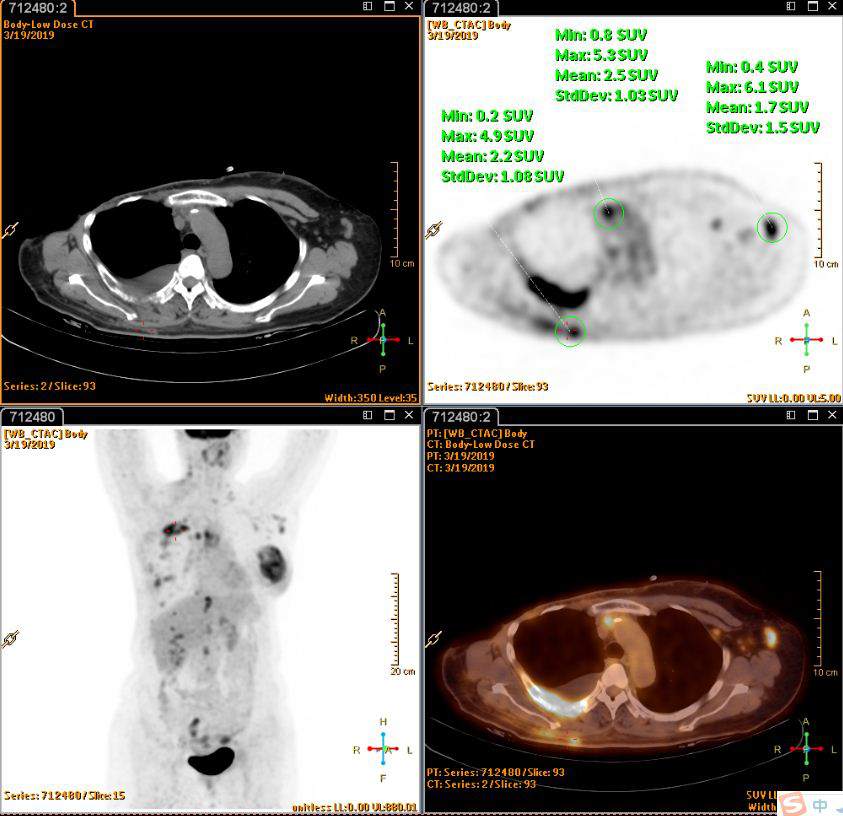

PET(2019-3-20):1.右乳癌术后改变,左侧乳腺腺体密实、左乳头周围皮肤增厚,葡萄糖代谢增高,考虑乳腺癌;颈部、纵隔、左侧腋窝、腹腔及腹膜后多发淋巴结转移,右侧胸膜转移,多发骨转移,多发肌肉转移;2.右侧液气胸,右肺炎症;肺下叶外基底段小结节,建议观察。

张2.png

图2